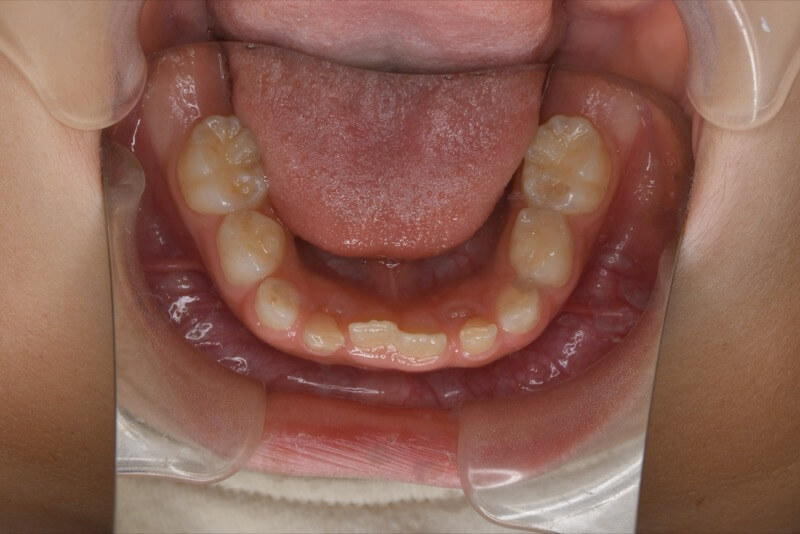

治療前

前歯が反対に咬んでいる。

前歯部反対咬合

前歯の反対咬合を可撤式の装置で改善しました。引き続き永久歯列完成まで経過を追って治療致します。